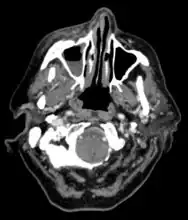

Imaging

Imaging is often performed, such as CT scan of lungs and sinuses.[38] Signs on chest CT scans, such as nodules, cavities, halo signs, pleural effusion and wedge-shaped shadows, showing invasion of blood vessels may suggest a fungal infection, but does not confirm mucormycosis.[16] A reverse halo sign in a person with a blood cancer and low neutrophil count, is highly suggestive of mucormycosis.[16] CT scan images of mucormycosis can be useful to distinguish mucormycosis of the orbit and cellulitis of the orbit, but imaging may look identical to those of aspergillosis.[16] MRI may also be useful.[39]

CT scan chest of person treated for acute myeloid leukaemia, presented with cough, fever and shortness of breath.